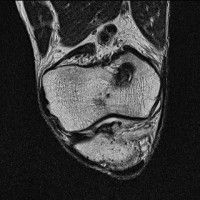

무릎 mri 간단히 봐주실 수 있으시나요 ㅠㅠ

안녕하세요 8년전 십자인대 수술하고 최근 무리한 운동에 무릎 불편감이 생겨서

mri 찍었습니다.

진단결과는 첫 찍은 병원에서 활액막염 이라는 진단을 받았습니다. 혹시 봐주실 수 있으실까요?

올라온 MRI가 단편적이라서 정확한 진단에 어려움이 있지만 십자인대에는 큰 이상이 있지는 않은것 같으며, 무릎관절내 물이 있는 것으로 보아 활액막염의 진단이 맞을 것 같습니다.

하지만 단편적인 영상이기 때문에 촬영병원에서 정확한 판독지 등을 받으시는 것이 좋겠습니다.